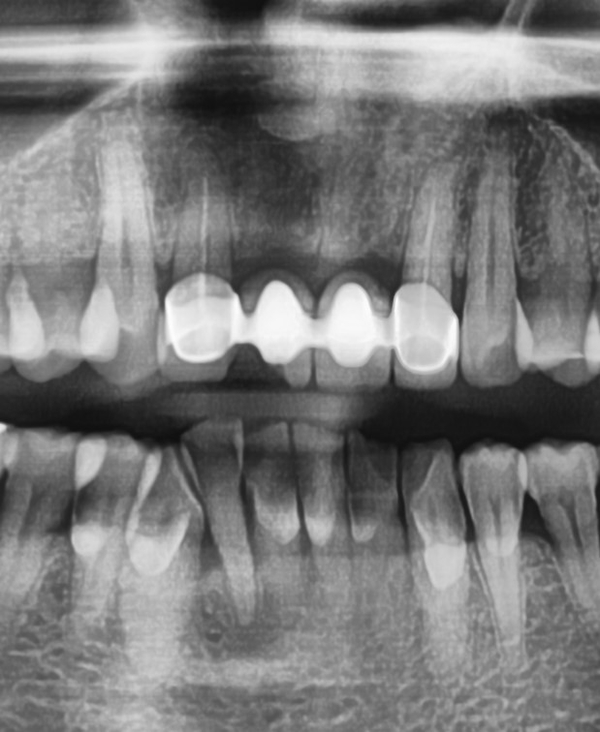

이 몇 십년동안 쓰신 브릿지는 위 엑스레이 처럼

중간 치아 2개는 발치하고 양 옆 치아를 걸어 브릿지를 만든 것입니다.

재료는 PFM으로

깨진 부위는 금속위에 도자기를 올린 부위로 도자기가 충격에 의해 깨져나간 것입니다.

환자분과 상담후, 오래된 브릿지고 몇 십년전 잇몸에 맞춘 상태였기 때문에 잇몸이 내려가면서 브릿지에 싸여있어야 할 치아도 노출 되어 있었기 때문에 브릿지를 새로 제작하기로 하였습니다.